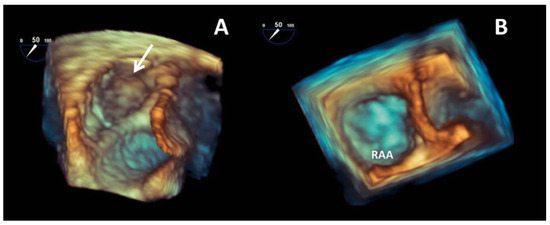

Atrial fibrillation is a cause of left atrial thrombus leading to cardioembolic stroke, which can be effectively prevented with oral anticoagulation. Right atrial appendage thrombus is a rare complication of atrial fibrillation that can also lead to cardioembolic pulmonary embolism. We present the [...] Read more.

Atrial fibrillation is a cause of left atrial thrombus leading to cardioembolic stroke, which can be effectively prevented with oral anticoagulation. Right atrial appendage thrombus is a rare complication of atrial fibrillation that can also lead to cardioembolic pulmonary embolism. We present the case of a 71-year-old male with atrial fibrillation, thrombus in the right atrial appendage and pulmonary embolism. Full article

Show Figures

Figure 1